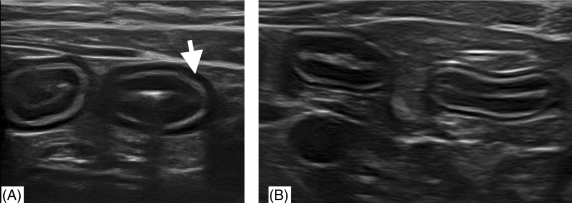

low grade에서는 종양이어도 층간 구조 소실이 보이지 않기 때문에 함부로 종양이다, 종양이 아니다를 말해서는 안된다.

high grade라면 그냥 초음파만 봐도 악해 보이니 바로 감별이 가능하긴 하다